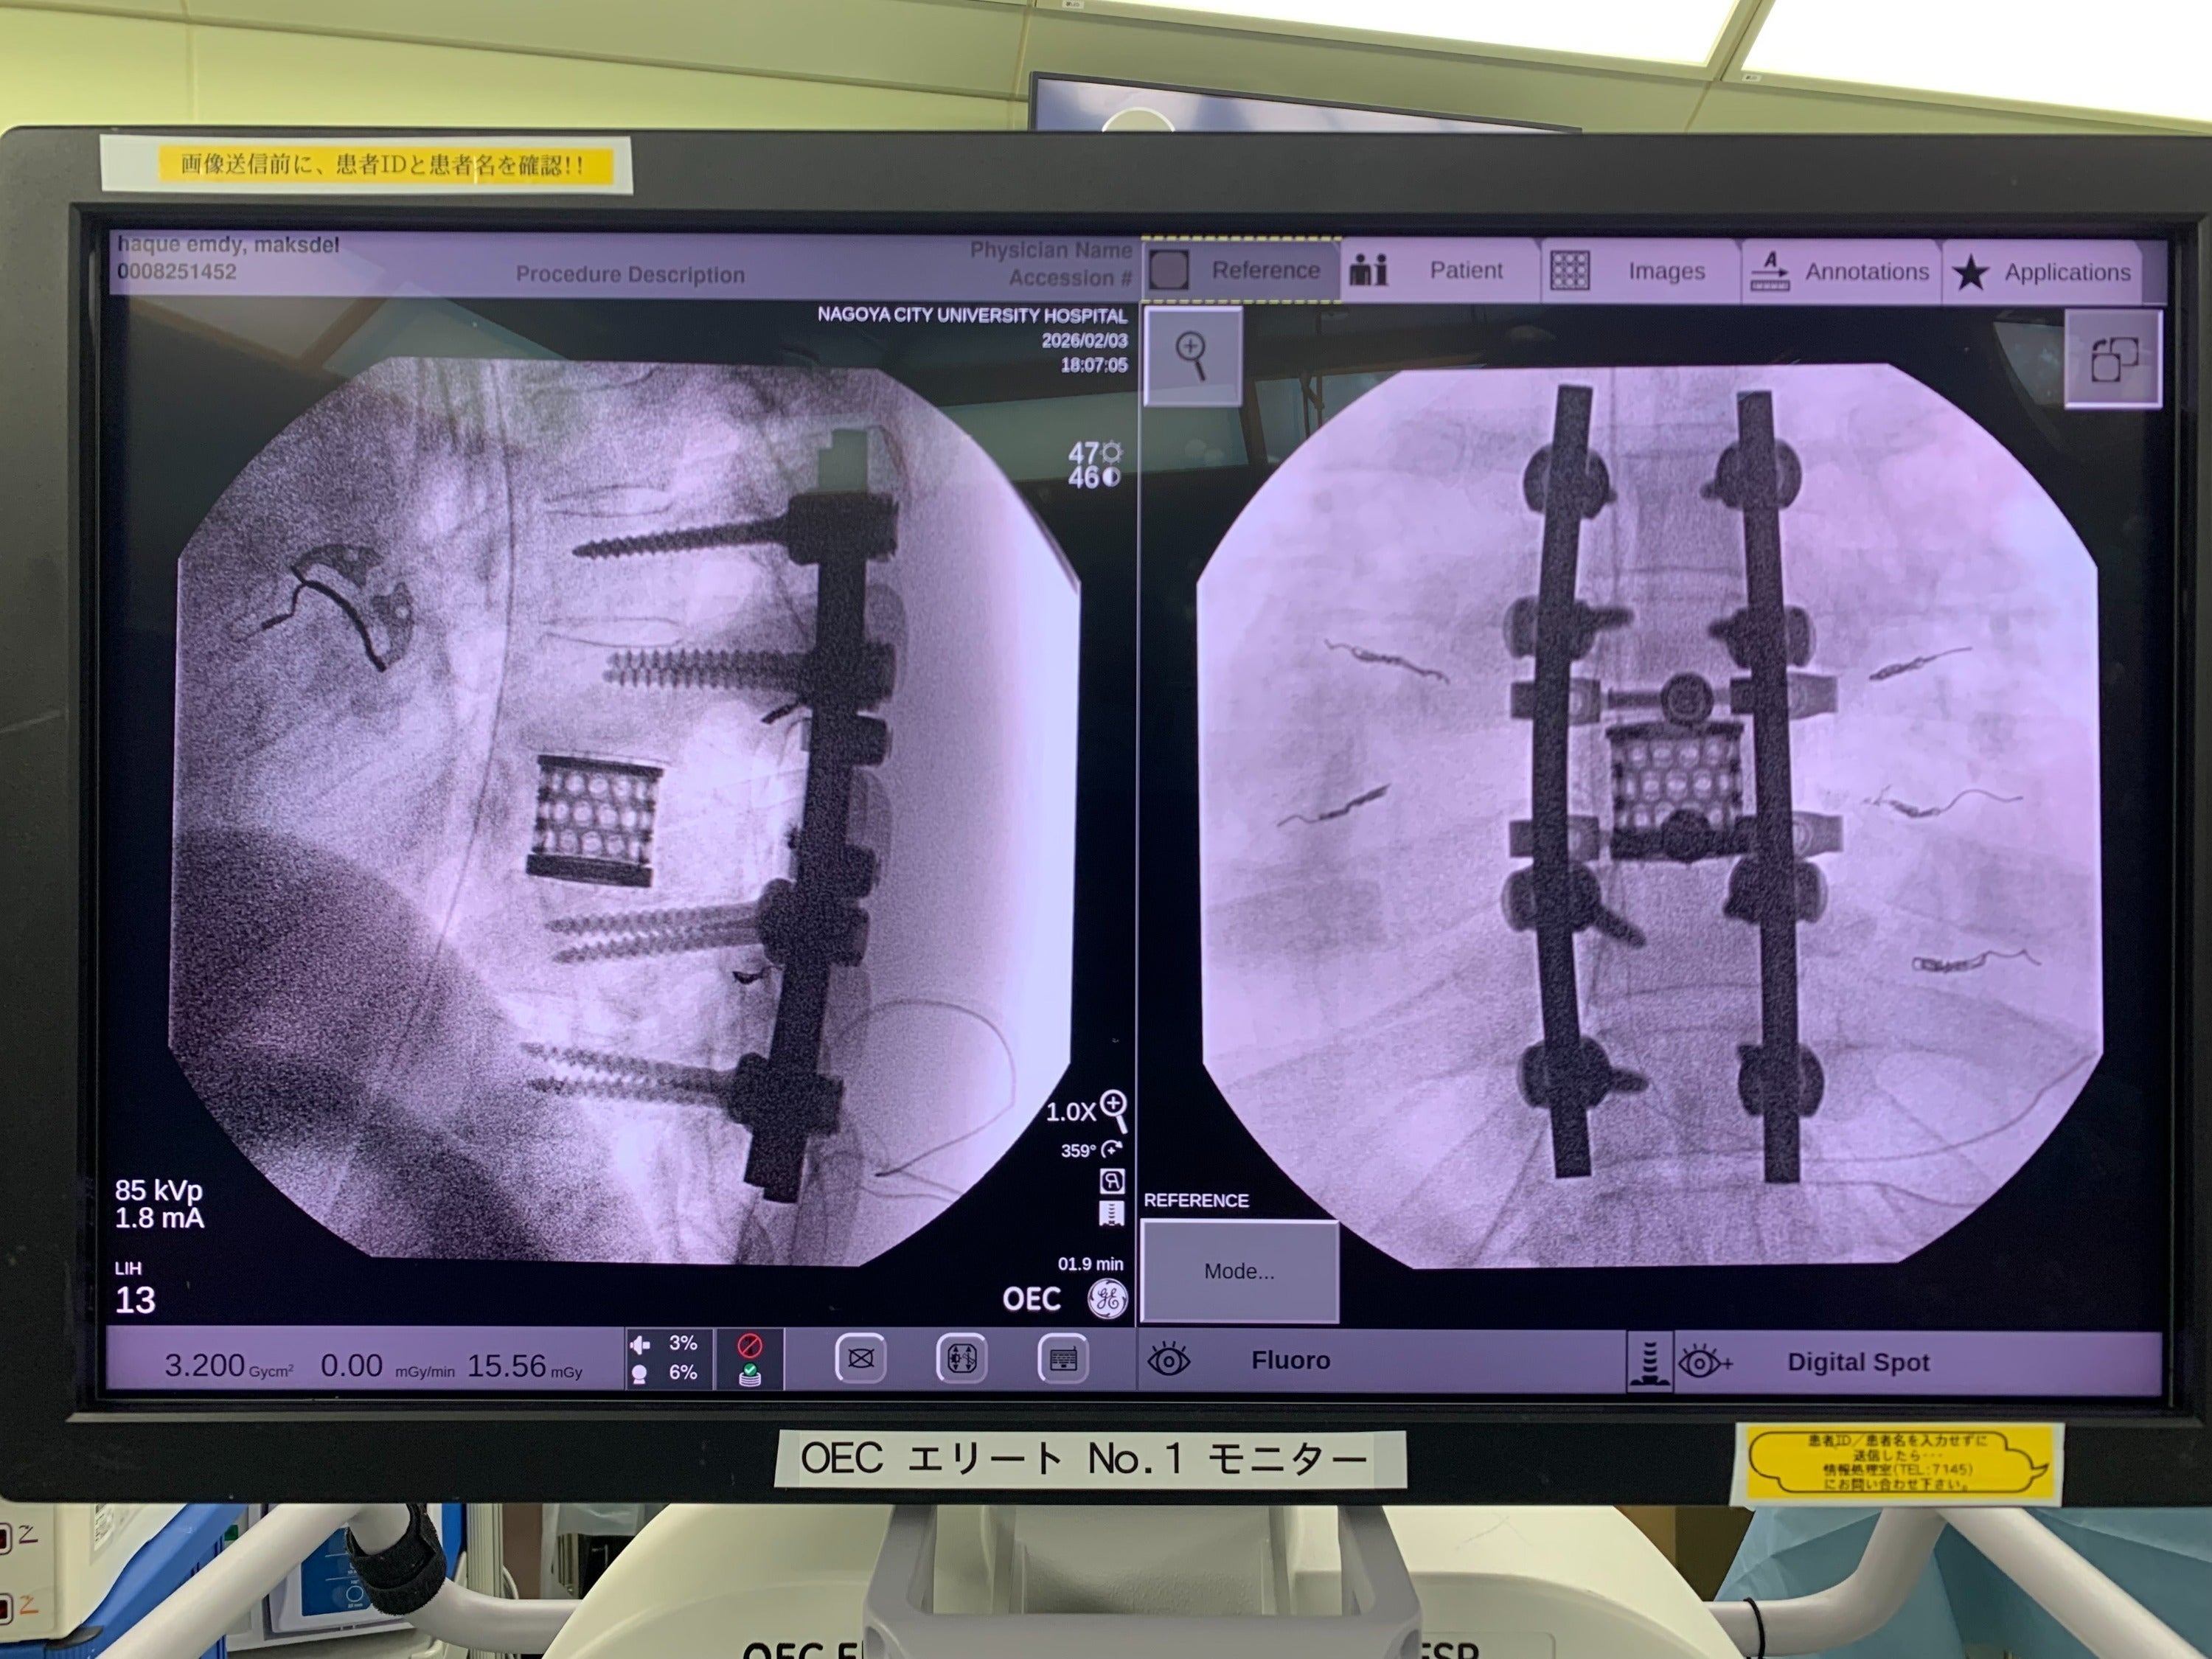

ハクさんは 7時間を超える大きな手術 を受けました。

脊椎の腫瘍を取り除く手術はとても難しく、日本でも限られた医師しか行うことができない高度な手術です。

母国バングラデシュでは、この治療を受けることはできません。